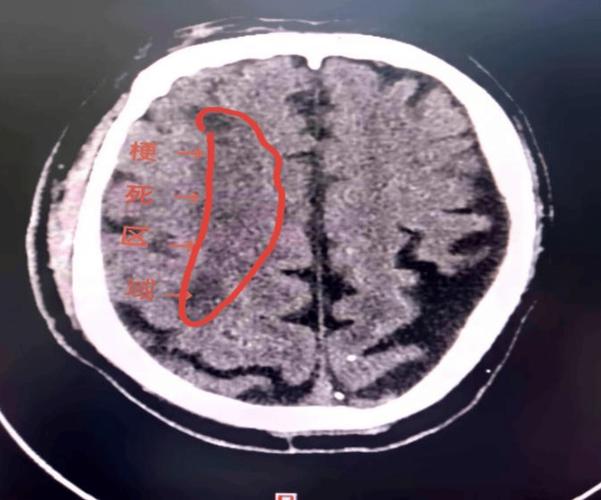

• 清晰的低密度灶:坏死的脑组织会变成明显的、边界相对清晰的低密度(发黑)区域,这时,CT诊断脑梗就非常明确和容易了。

• 占位效应:大面积的脑梗死后,周围脑组织会因为水肿而产生挤压,导致脑室受压变形,中线结构移位。